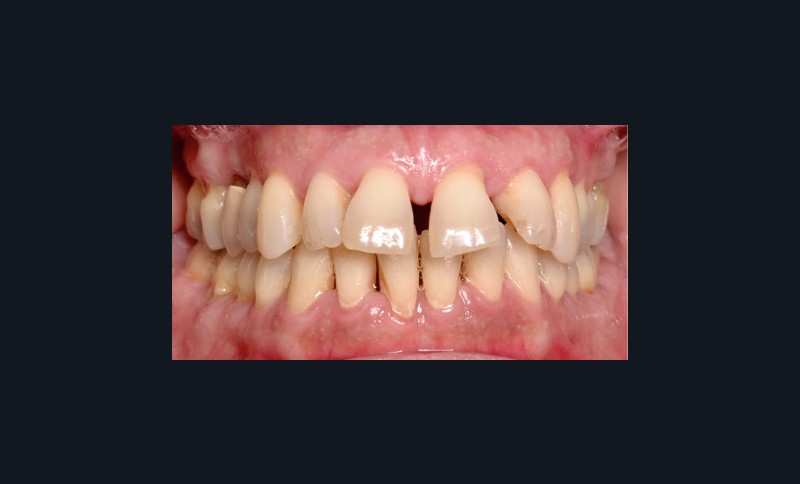

À l’examen endo-buccal (fig. 2), on note une formule dentaire complète (absence des 8) avec présence de restaurations multiples étanches, un bon contrôle de plaque et une parodontite de stade 4 grade C stabilisée [3], des récessions gingivales et des mobilités dentaires généralisées (degré 2, classification de Miller). L’arcade mandibulaire présente une courbe de spee importante avec égression du bloc incisivo-canin. Les milieux inter-incisifs sont alignés, le recouvrement est normal, le surplomb est augmenté à 3 mm et associé à des diastèmes et de la vestibulo-version des incisives maxillaires. Les relations antéro-postérieures canine et molaire sont en Classe I d’Angle.